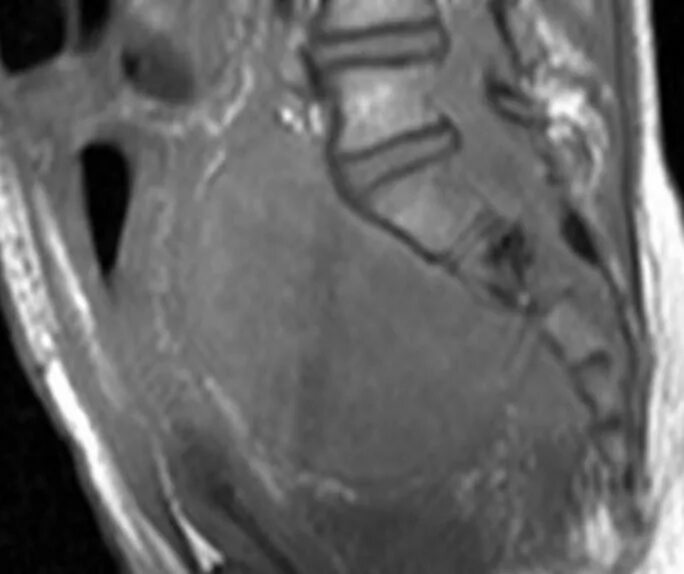

Саркома мрт